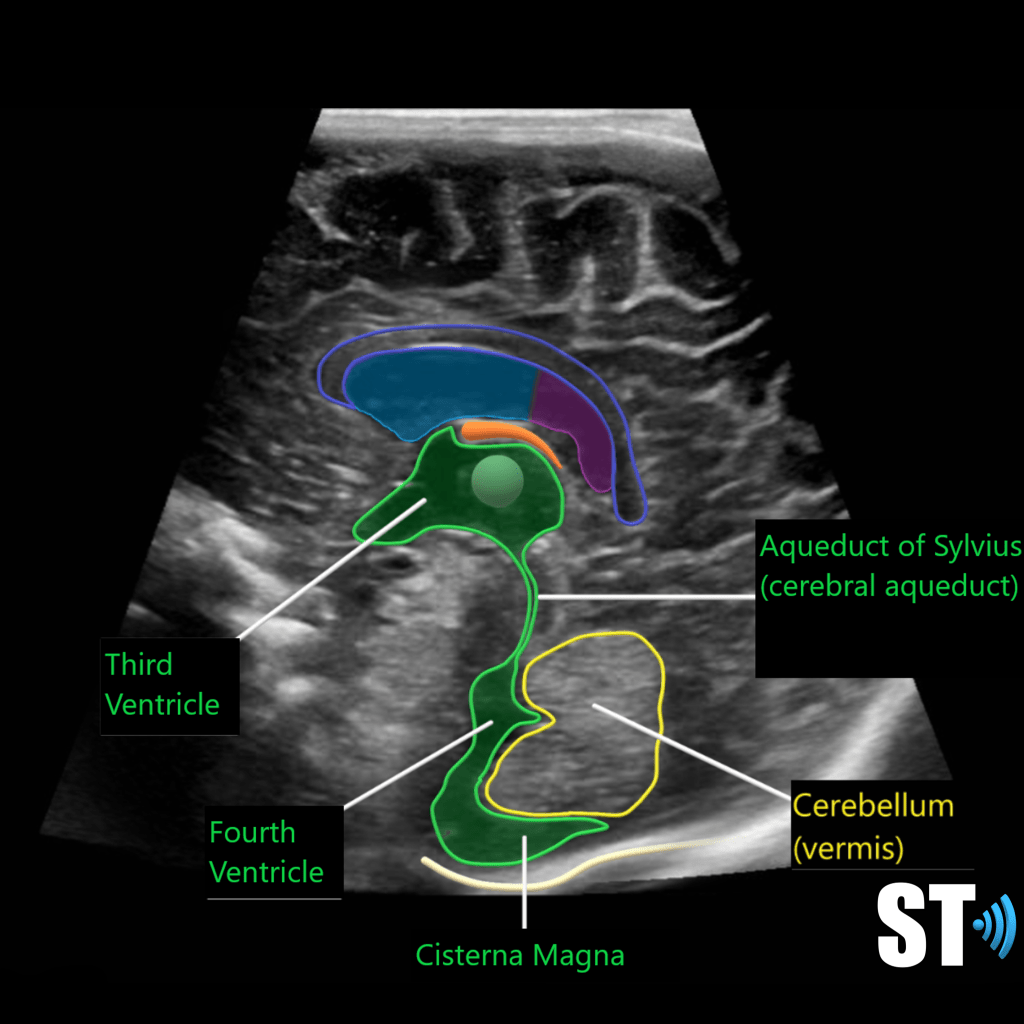

The ventricular system is a series of chamber deep within the brain that collect and allow the flow of cerebrospinal fluid. The main components are the paired lateral, third and fourth ventricles.

Within each ventricle is the choroid plexus which is a network of cells that line the bodies of the lateral ventricles, the roof of the third ventricle and a little bit in the fourth ventricle. The choroid plexus creates the cerebrospinal fluid.

The cerebellum is another occipital bi-lobe structure which is also important motor control. It is located in the posterior fossa.